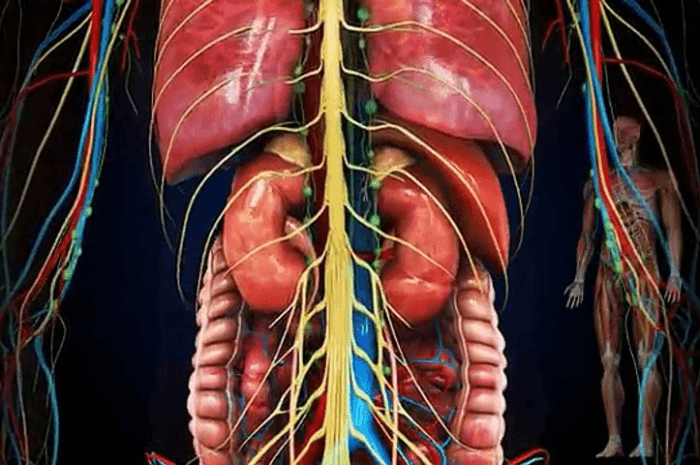

Continue ReadingDiabetes & Associated Complications